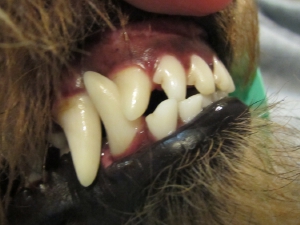

まずは全身麻酔にて乳歯犬歯を抜歯します。

実際移動を予定している犬歯の位置は青い歯で示した場所です。犬歯を矢印で示すように移動させます。